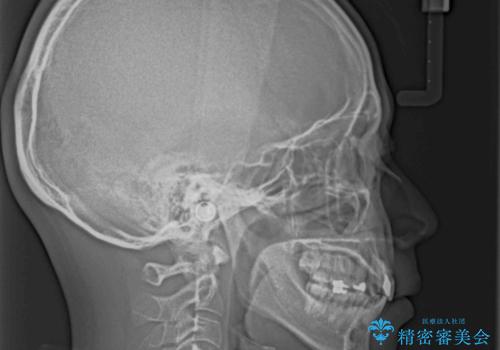

- 飛び出した前歯を気にして来院された患者様です。

口元を引っ込めるために上下左右の第一小臼歯4本を抜歯することとしました。